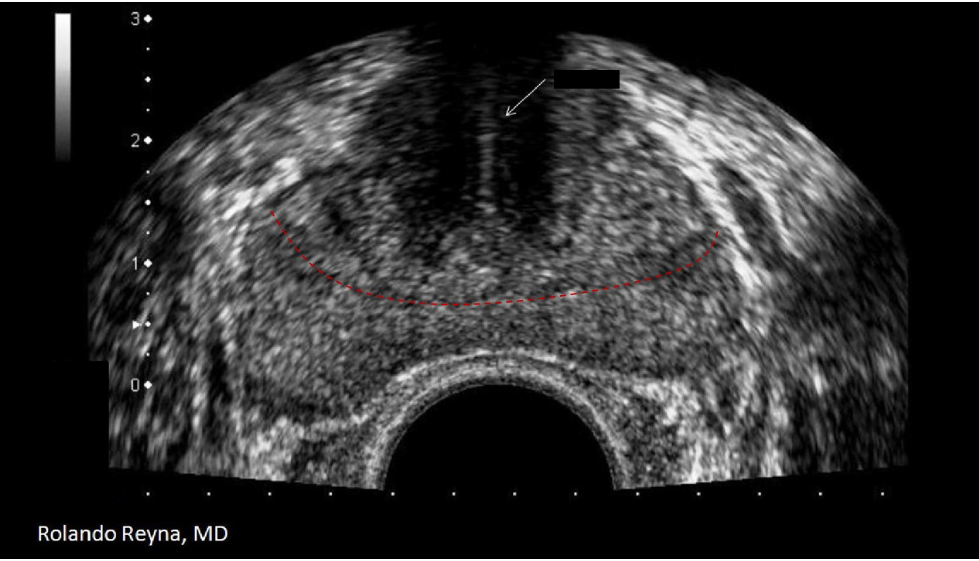

The red dotted line separates what two zones of the prostate?

B. transitional and peripheral

The white arrow indicates the urethra and the red dotted lines separate the transitional and peripheral zones.

The white arrow on the image indicates:

D. urethra